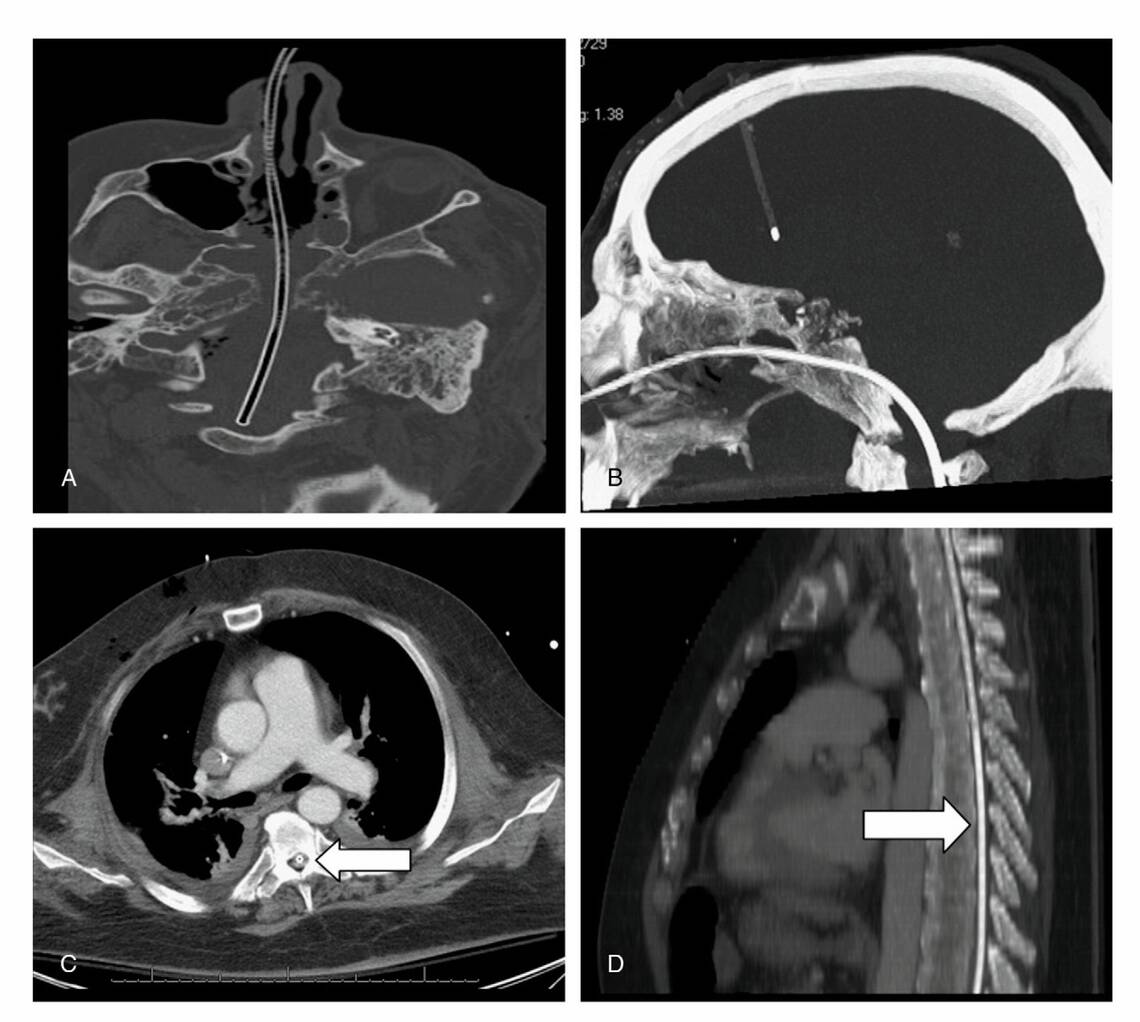

Die Folgen einer intrathorakalen Anlage sind entsprechend pulmonale Blutungen, pleurale Penetration, Pneumothorax mit Empyem und Sepsis. Ein erhöhtes Risiko für Fehlanalgen treten bei Patienten mit endotrachealem Tubus, Bewusstseinsstörung, verminderten Schutzreflexen und bei wiederholten Fehlanlagen auf, vor allem im Nachtdienst und bei geringer Erfahrung der Anwender (Braun et al. 2011). Ösophagusperforationen und craniale Insertionen (Abb. 1) sind selten bis extrem selten (Freij et al. 1997, Hanna et al. 2012).

Seltene Komplikation

Ein 57-jähriger männlicher Patient, Zustand nach transnasalen neurochirurgischen Operationen, entfernt sich nachts die Ernährungssonde. Der diensthabende Arzt legt in Eile eine neue Sonde. Im Zuge der Anlage entwickelt der Patient eine Hemiplegie, später eine vollständige Tetraparese. Ursache hierfür ist eine versehentliche Anlage der Sonde durch die Schädelbasis in den Spinalkanal, wie die axialen (A, C) und sagittalen (B, D) CT-Fotos zeigen. Trotz unmittelbaren restituierenden Operationen verstirbt der Patient nach sieben Monaten in einem Pflegeheim (Hanna et al. 2012).